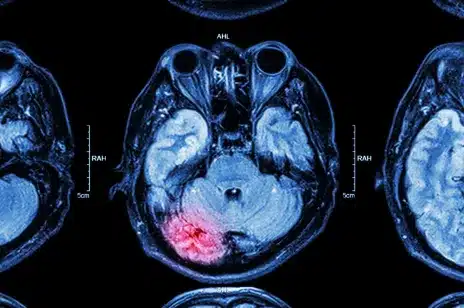

Inmate Suffered Brain Injuries, Sheriff Testifies

Miami, FL – The family of a former inmate of the Broward County Jail has filed a federal civil rights lawsuit and the former sheriff, Ken Jenne, has been named personally. This could mean that any damages the jury awards could result in Jenne having to pay out of his own pocket. Other defendants include […]